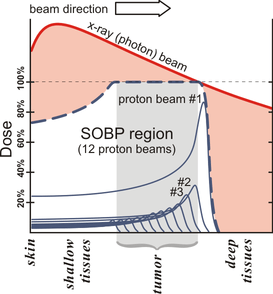

Because of their relatively large mass, protons have little lateral side scatter in the tissue; the beam does not broaden much, stays focused on the tumor shape and delivers only low-dose side effects to surrounding tissue. All protons of a given energy have a certain range; very few protons penetrate beyond that distance.[4] Furthermore, the dose delivered to tissue is maximized only over the last few millimeters of the particle’s range; this maximum is called the Bragg peak, often referred to as the SOBP.[5]

To treat tumors at greater depths, the proton accelerator must produce a beam with higher energy, typically given in eV or electron volts. Proton therapy treats tumors closer to the surface of the body with lower energy protons. Accelerators used for proton therapy typically produce protons with energies in the range of 70 to 250 MeV. Adjusting proton energy during the treatment maximizes the cell damage the proton beam causes within the tumor. Tissue closer to the surface of the body than the tumor receives reduced radiation, and therefore reduced damage. Tissues deeper in the body receive very few protons, so the dosage becomes immeasurably small.[4]

In most treatments, protons of different energies with Bragg peaks at different depths are applied to treat the entire tumor. These Bragg peaks are shown as thin blue lines in the figure to the right. The total radiation dosage of the protons is called the spread-out Bragg peak (SOBP), shown as a heavy dashed blue line in figure to the right. It is important to understand that, while tissues behind or deeper than the tumor receive almost no radiation from proton therapy, the tissues in front of or shallower than the tumor receive radiation dosage based on the SOBP.

The figure at the right of the page shows how beams of X-rays (IMRT; left frame) and beams of protons (right frame), of different energies, penetrate human tissue. A tumor with a sizable thickness is covered by the IMRT spread out Bragg peak (SOBP) shown as the red lined distribution in the figure. The SOBP is an overlap of several pristine Bragg peaks (blue lines) at staggered depths.